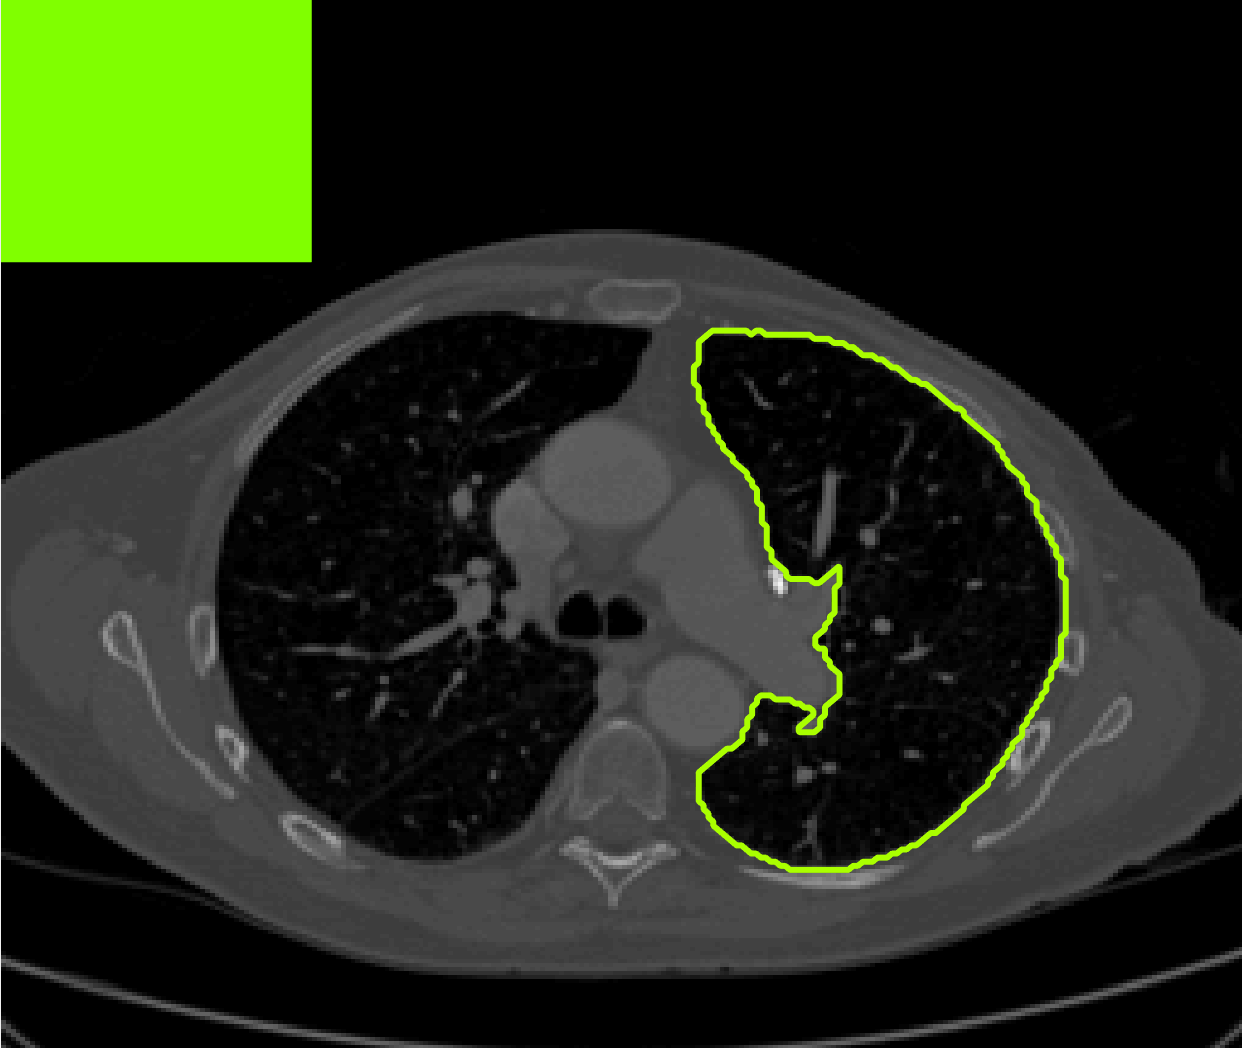

The motivation for this work comes from observing contradictions in using piecewise-constant intensity fitting terms in selective segmentation. Whilst good results are possible with this approach, the exceptional cases lead to severe limitations in practice. This is quite common in medical imaging as demonstrated in Fig. 1, where the target foreground has a low intensity. Given that the corresponding background includes large regions of low intensity, the optimal average intensities for this segmentation problem are and . For cases where , we see that by (1), almost everywhere in the domain . This means that it is very difficult to achieve an adequate result, without an over-reliance on the user input or parameter selection.

for and as defined in (33). This is consistent with respect to the intensities of the observed object and the concept of selective segmentation. In Fig. 3 we see the difference between CV and the proposed fitting terms for given user input on a CT image. For the CT image, the CV fitting terms are near 0 within the target region. This is despite there being a distinct homogeneous area with good contrast on the boundary. This illustrates the problem we are aiming to overcome. With the proposed fitting term this phenomenon should be avoided in cases like this. By defining as in (33) there is no contradiction if the foreground and background intensities of the target region are similar.